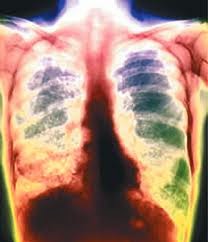

Penyakit TBC/TB dapat menyerang siapa saja (tua, muda, laki-laki ataupun perempuan), dan yang paling berbahaya lagi, penyakit ini bisa menular kepada siapa saja. Penyakit TBC adalah merupakan suatu penyakit yang tergolong dalam infeksi yang disebabkan oleh bakteri Mikobakterium tuberkulosa.Penyakit TBC disebabkan oleh bakteri Mikobakterium tuberkulosa, Bakteri ini berbentuk batang dan bersifat tahan asam sehingga dikenal juga sebagai Batang Tahan Asam (BTA). Jenis bakteri ini pertama kali ditemukan oleh seseorang yang bernama Robert Koch pada tanggal 24 Maret 1882, Untuk mengenang jasa beliau maka bakteri tersebut diberi nama baksil Koch. Bahkan penyakit TBCpada paru-paru pun dikenal juga sebagai Koch Pulmonum (KP).

Penyebab utama penyakit ini adalah bakteri, Mikobakterium tuberkolosa, dan penyebaran bakteri ini dari penderita TBC paru melalui percikan dahak, Pada waktu batuk atau bersin yang menyebar ke udara. Kuman yang sudah tersebar di udara akan masuk melalui pernafasan kemudian menyebar kebagian paru dan tidak menutup kemungkinan akan menyebar ke organ-organ tubuh lain.